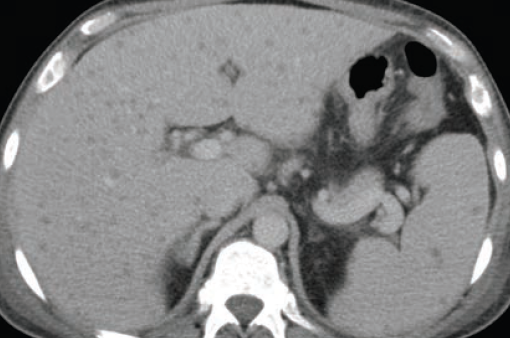

Dx?

Candidasis

Systemic fungal infection that may seed the liver and the spleen

CT shows multiple tiny hypoattenuating microabscesses in the liver and the spleen which can be rim-enhancing

DDX for hypoattenuating liver lesions: metastatic disease, lymphoma, biliary hamartomas or Caroli disease